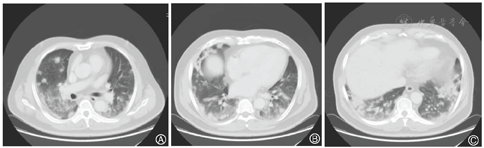

患者,男,56岁,因发热、咳嗽、咳痰伴活动后胸闷3 d于2019年9月10日入院。患者3 d前无诱因出现发热,体温在38 ℃左右,无畏寒、寒战,无盗汗,发热无明显规律性,伴咳嗽,咳少许黄白痰,无胸痛、咯血,伴胸闷、憋气,活动后加重,无消瘦,无头晕、恶心、呕吐,门诊行胸部CT考虑双肺感染性病变,为进一步诊治收住院。患者入院的20 d前在日本出差时出现咽痛,自服感冒药物(具体不详)后好转。既往有“冠心病、高血压”病史4年,2015年行冠脉造影示冠状动脉肌桥,无吸烟史,无禽类、粉尘、工业毒物接触史。体格检查:体温36.5 ℃,脉搏84次/min,呼吸23次/min,血压137/75 mmHg(1 mmHg=0.133 kPa),神志清,全身皮肤无皮疹,口唇发绀,双肺呼吸音粗,双下肺可闻及湿性啰音,心率84次/min,律齐,未闻及杂音。腹软,无压痛、反跳痛,双下肢无浮肿,四肢肌力正常。入院后查动脉血气分析(未吸氧):pH为7.374,二氧化碳分压为39.4 mmHg,氧分压为52.6 mmHg,血氧饱和度为84.8%,乳酸为1.1 mmol/L;血常规:白细胞计数为7.68×109/L,中性粒细胞百分比为 72.1%,淋巴细胞百分比为17.2%,红细胞计数为4.47×1012/L,血沉为16 mm/h;血生化:白蛋白为36.3 g/L,葡萄糖为6.44 mmol/L,乳酸脱氢酶为284 U/L,C反应蛋白为30.9 mg/L,三酰甘油为2.25 mmol/L;血凝常规:纤维蛋白原含量为4.67 g/L;肺肿瘤标志物CYFRA21-1为11.3 ng/ml;降钙素原为0.052 μg/L;病原学检查:半乳甘露聚糖试验(GM试验)为0.38 μg/L;痰细菌培养、真菌涂片、结核菌涂片阴性;肺炎支原体抗体、衣原体抗体、呼吸道合胞病毒抗体、出血热病毒抗体、真菌葡聚糖、巨细胞病毒核酸检测均阴性;免疫相关:抗核抗体(ANA)、抗环瓜氨酸肽抗体(CCP)、抗中性粒细胞胞浆抗体(ANCA)均阴性;机体细胞免疫评价正常;尿常规、大便常规、肌钙蛋白、脑钠肽均正常;乙肝表明抗原、丙肝抗体、梅毒抗体、HIV抗体均阴性;心电图示窦性心律、心电轴中度左偏、ST-T异常;胸部CT考虑双肺感染,建议治疗后复查,心影饱满,冠脉钙化,两侧胸膜略增厚(图1A~C)。入院后给予经鼻高流量湿化氧疗(氧浓度50.0%,氧流量50 L/min),美洛西林舒巴坦(2.5 g,1次/12 h)联合左氧氟沙星(0.6 g,1次/d)抗感染,奥司他韦胶囊(75.0 mg,2次/d)抗病毒,多索茶碱(0.3 g,1次/d)扩张支气管,溴己新(4.0 mg,2次/d)止咳化痰,低分子肝素钠(5 000 U,ih,1次/d)抗凝,硝苯地平缓释片(10.0 mg,2次/d)降压治疗,患者体温逐渐降为正常,但活动时胸闷无改善,经皮血氧饱和度在95.0% 左右(上述氧疗情况下),考虑抗感染解痉平喘治疗效果不佳,不除外间质性肺病,遂于9月14日加用甲泼尼龙(40.0 mg,1次/12 h)静滴,自觉症状略有好转,于9月17日复查胸部CT示双肺片状影较前增多(图2A~C),提示疾病进展,与患者及家属沟通后于9月17日行床旁支气管镜检查,镜下见左右肺各叶段支气管通畅,黏膜轻度充血,可见少量白色泡沫样分泌物,未见狭窄、出血及新生物(图3),于右肺下叶后基底段行肺泡灌洗及透壁肺活检,肺泡灌洗液(BALF)细胞分类示淋巴细胞百分比为63.0%,中性粒细胞百分比为24.0%,巨噬细胞百分比为8.0%,上皮细胞百分比为5.0%;BALF细菌、真菌涂片和培养均阴性;BALF结核菌涂片、结核菌核酸扩增检测(Gene Xpert)均阴性;BALF脱落细胞学检查阴性;BALF-GM试验0.55 ng/ml;BALF病原微生物宏基因组检测(NGS)示产黑色素普雷沃菌(序列数12)、龋齿罗氏菌(序列数7)、简明弯曲杆菌(序列数1);支气管镜肺活检病理考虑肺间质纤维化(图4)。患者对治疗反应不佳,为排除肿瘤于9月20日行正电子发射计算机断层显像(PET-CT)示双肺多发斑片影、结节灶,大部分见支气管充气征,部分结节边缘见分叶和毛刺,SUVmax 6.4,考虑感染性疾病,霉菌感染可能性大,肉芽肿性炎和MALT淋巴瘤不除外(图5)。请北京协和医院专家会诊,考虑ILD,不除外结缔组织病相关,建议加大甲泼尼龙(80.0 mg,1次/8 h)用量,升级抗生素为美罗培南(1.0 g,1次/8 h),完善肌炎谱13项示抗Jo-1抗体阳性,最终诊断为抗Jo-1抗体综合征,加用环磷酰胺(0.4 g,1次/周)静滴8次,并逐渐减少甲泼尼龙用量,患者胸闷症状明显好转,2019年11月18日复查胸部CT示肺内病变较前明显吸收好转(图6A~C),随访1年,病情稳定。